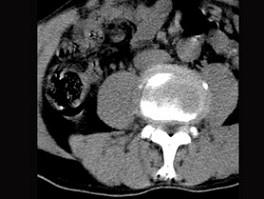

问题 男,45岁,腰痛,请结合所提供图像,选择最佳答案 ( )

选项 A、腰椎骨质增生 B、前纵韧带钙化 C、椎间盘突出 D、椎间盘未见异常 E、椎间盘膨出

答案 E